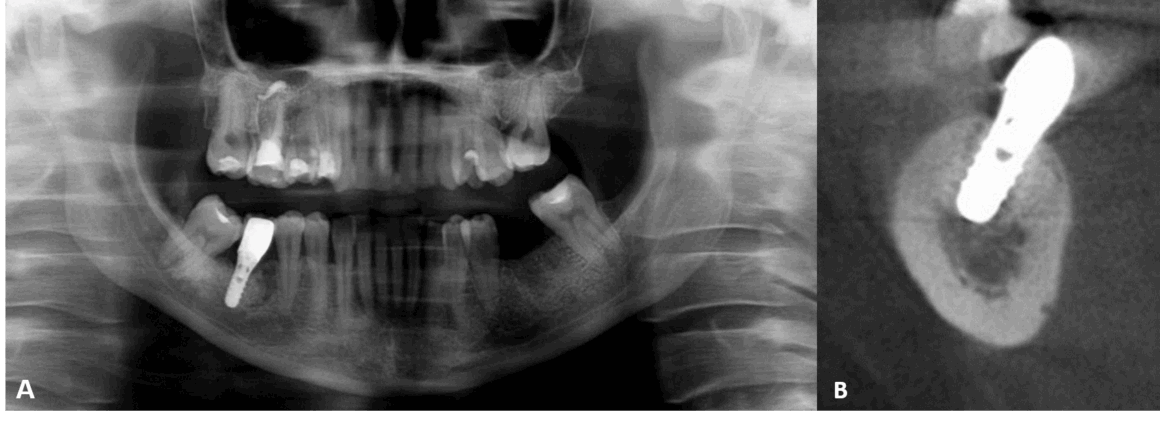

La sustitución dental con una restauración soportada por implantes es un método de tratamiento predecible y eficaz. Las tasas de éxito a largo plazo están relacionadas con el fenómeno de la osteointegración de los implantes dentales. Sin embargo, el proceso de osteointegración del implante puede verse afectado por factores como la estabilidad primaria del implante, que depende de la geometría del implante, la técnica quirúrgica y el estado del hueso, es decir, la densidad y el volumen óseos. Por lo tanto, un estado óseo insuficiente puede dar lugar a complicaciones clínicas durante la colocación del implante dental o durante el proceso de osteointegración. Una de estas afecciones puede ser el defecto óseo medular osteoporótico focal, lo cual es una zona radiotransparente asintomática que suele descubrirse de forma incidental durante un examen radiográfico. Puede tener diversos tamaños y formas sin expansión del hueso cortical de la mandíbula. El defecto óseo medular osteoporótico focal consiste en médula roja hematopoyética con cantidades variables de médula amarilla grasa. Esta afección suele encontrarse en la región posterior de la mandíbula en mujeres adultas. Además, el defecto óseo medular osteoporótico focal se localiza principalmente en zonas edéntulas donde se ha realizado previamente una extracción dental. La falta de estabilidad primaria debido a esta condición puede provocar el desplazamiento o incluso la migración del implante hacia la mandíbula.

Fig.1

El tratamiento consta en rellenar el foco osteoporótico con sustituto óseo y atornillar el implante a nivel tisular, que tiene un cuello y un hombro. Se eligió este tratamiento para evitar posibles complicaciones relacionadas con la lesión del nervio alveolar inferior y el desplazamiento del implante hacia la médula ósea mandibular. Algunos autores presentaron datos sobre el desplazamiento accidental del implante hacia el espacio medular del cuerpo mandibular en pacientes con defecto óseo medular osteoporótico focal. El desplazamiento importante del implante puede causar principalmente la compresión o incluso la lesión del nervio alveolar inferior. La situación puede complicarse con una nueva intervención quirúrgica para la extracción de los implantes, durante la cual pueden producirse lesiones secundarias en el nervio. La mayoría de los autores de los casos presentados utilizaron implantes a nivel óseo que no estaban suficientemente fijados en la capa cortical de la mandíbula. Por el contrario, en este estudio se utilizó un implante a nivel del tejido con un reborde prominente.